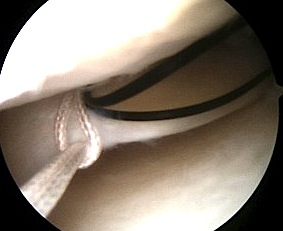

2. Inside out

Technique

Require

- double armed sutures with long flexible needles

- use single or double cannula system

Make open posteromedial / posterolateral approach

- retrieve the sutures needles as they exit the joint capsule

- protects neurological structures (saphenous / CPN) from needle or suture injury

- sutures then tied over capsule

- pass in flexion to protect structures

Pass the needles about the tear

- vertical or horizontal mattress sutures

- absorbable or non absorbable 2.0 suture

- every 2-3 mm

Tie sutures over capsule

- tie in extension or will break when patient extends leg